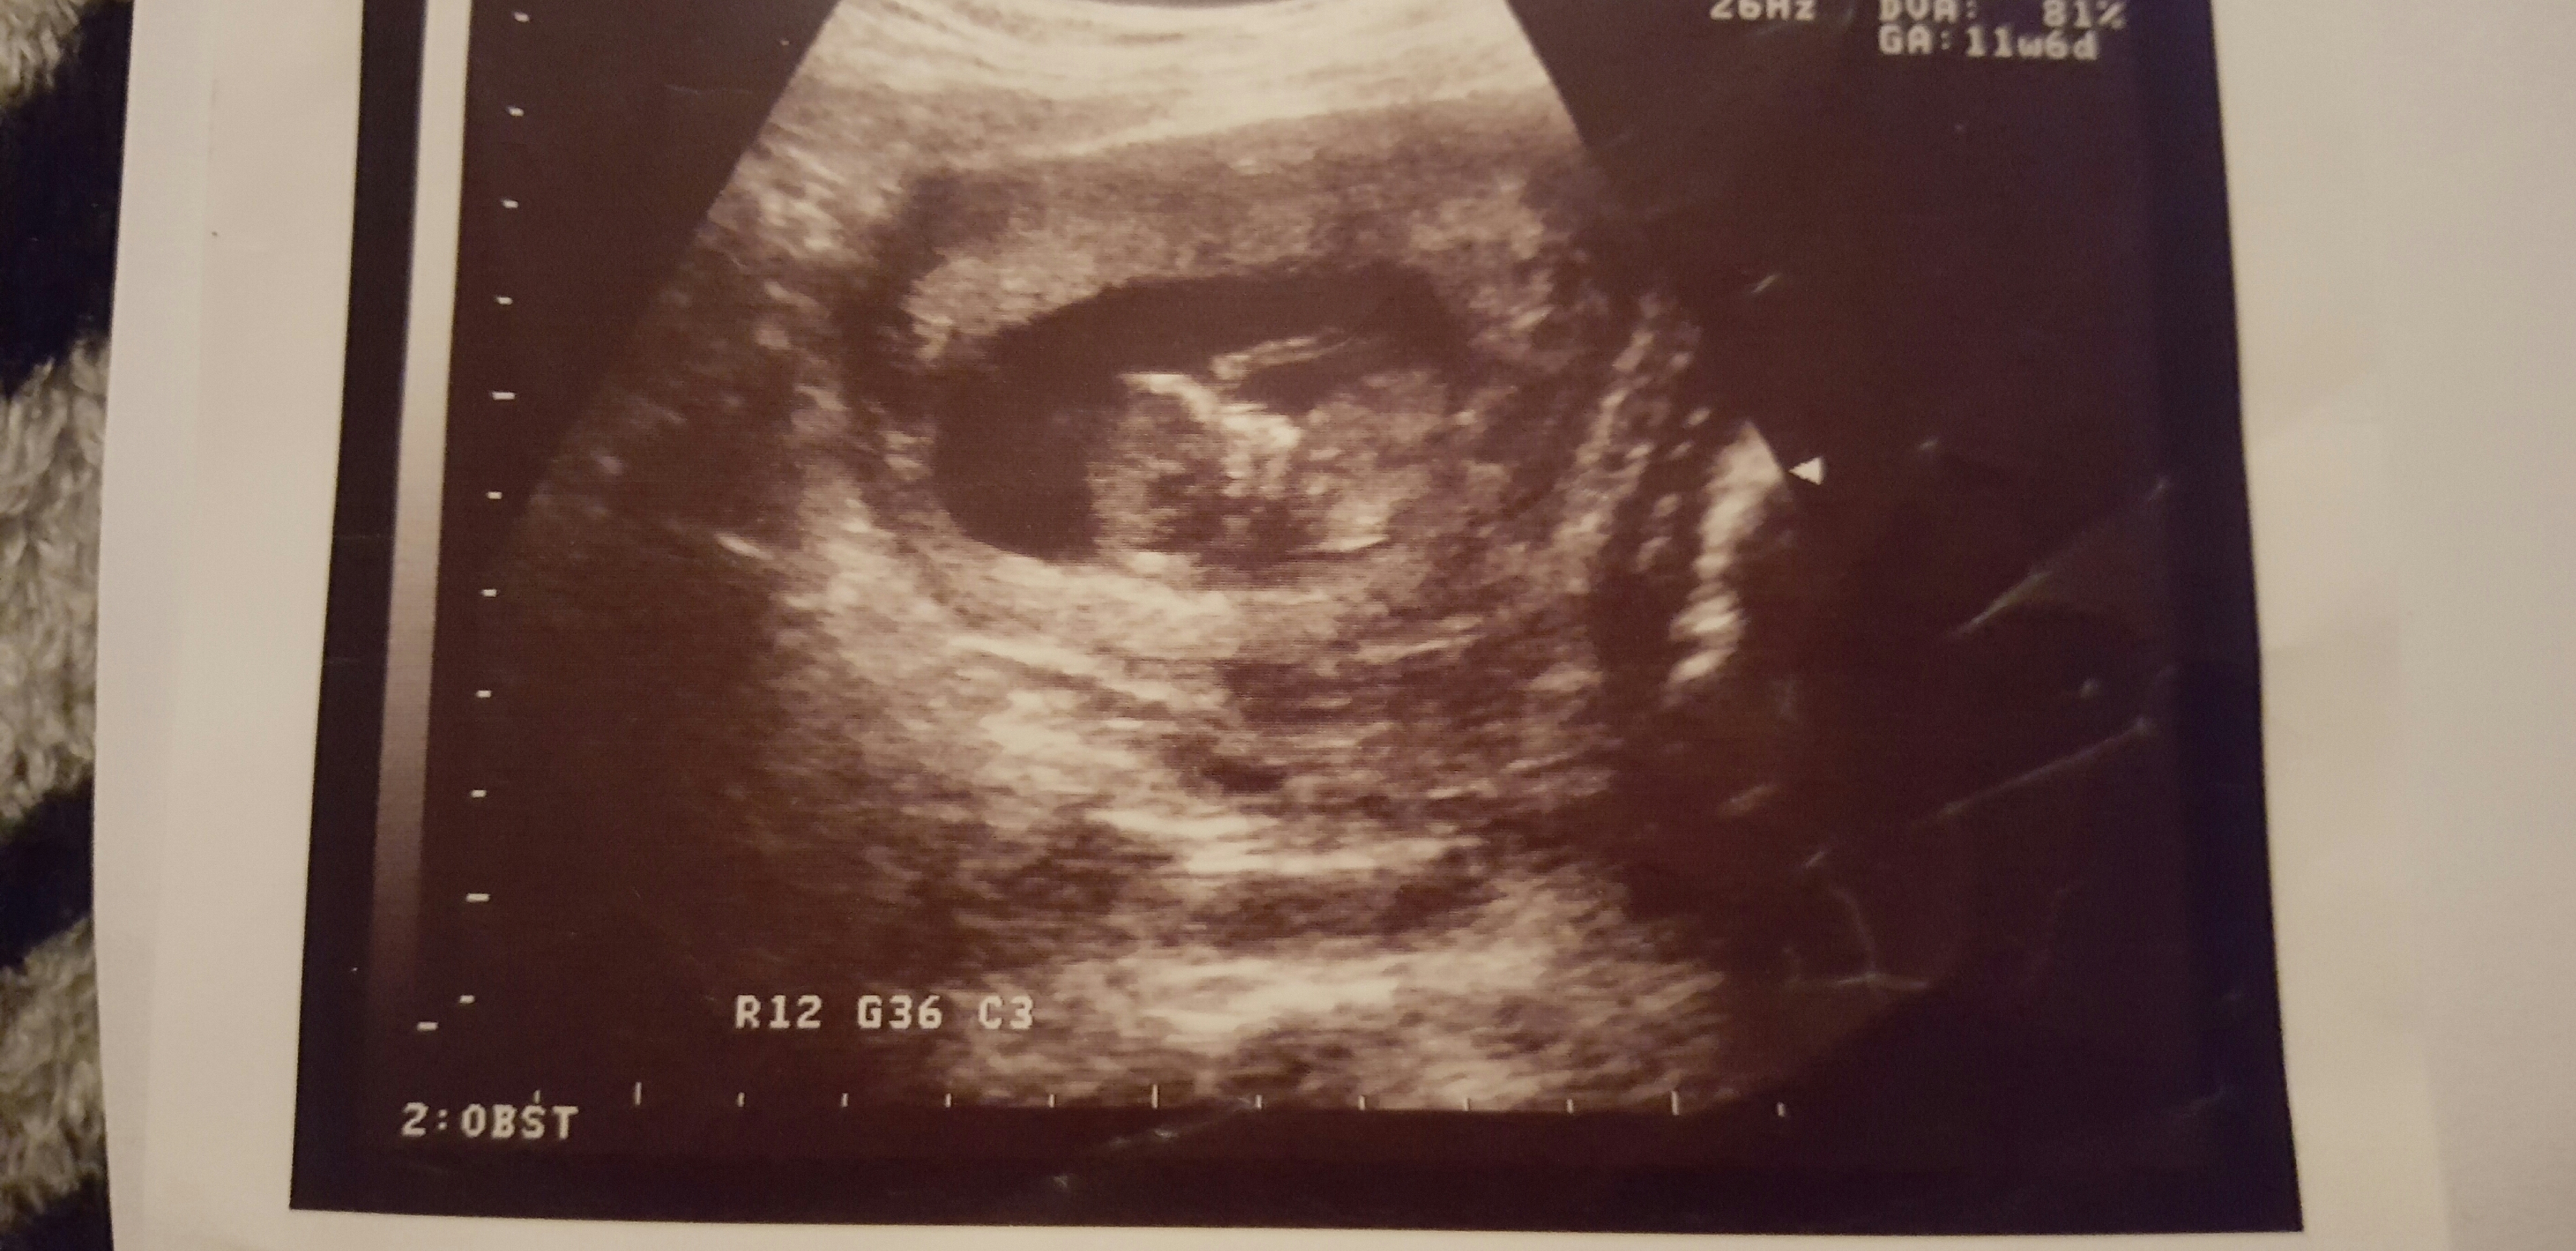

blue or pink what do you think? predictions please!!! 6 weeks 8 weeks 11weeks

Attachment 34253